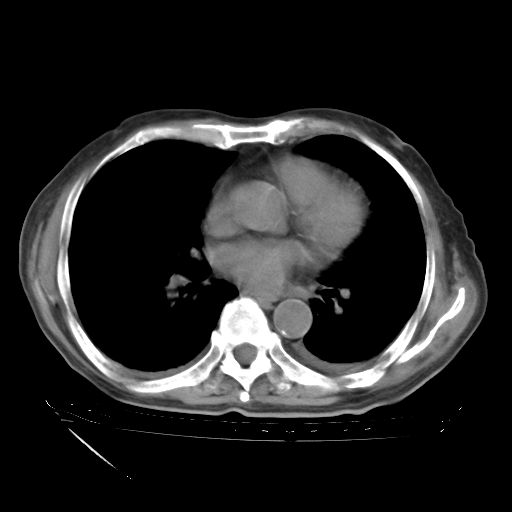

补充下:5月9日胸部CT:似乎已见双下肺胸腔积液了,鉴于目前有下肢水肿,肝功示:白蛋白低,应注意多浆膜腔积液(漏出液可能大?),需注意!

甲强龙80mg/日+抗结核治疗(异烟肼+利福霉素+乙胺丁醇)10天。复查肺部CT。

治疗10天肺部CT